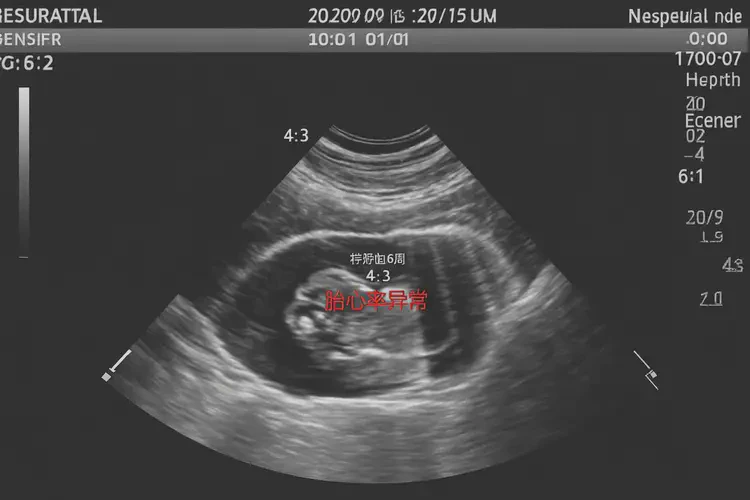

胎心率72次/分钟在怀孕第6周可能存在风险

怀孕第6周胎心率72次/分钟低于正常范围,通常正常胎心率在120-160次/分钟之间。胎心率受多种因素影响,包括胎儿发育阶段、孕妇健康状况等,因此不能仅凭一次测量结果判断胎儿是否能保住。

怀孕第6周胎心率72次/分钟可能提示风险,但不能仅凭一次测量结果判断胎儿是否能保住。孕妇应定期产检,密切监测胎心率及其他指标,遵循医生建议采取相应措施,以保障胎儿健康发育。